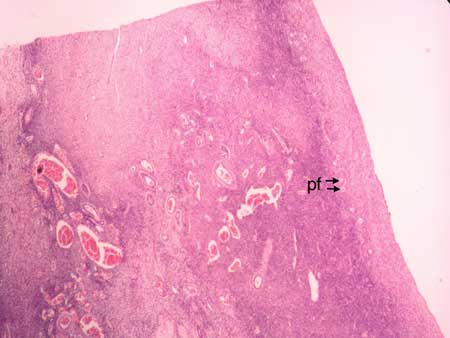

Slide: Ovary |

Microscope at 40X |

Primordial follicles pf = primordial follicle po = primary oocyte gc = granulosa cell |